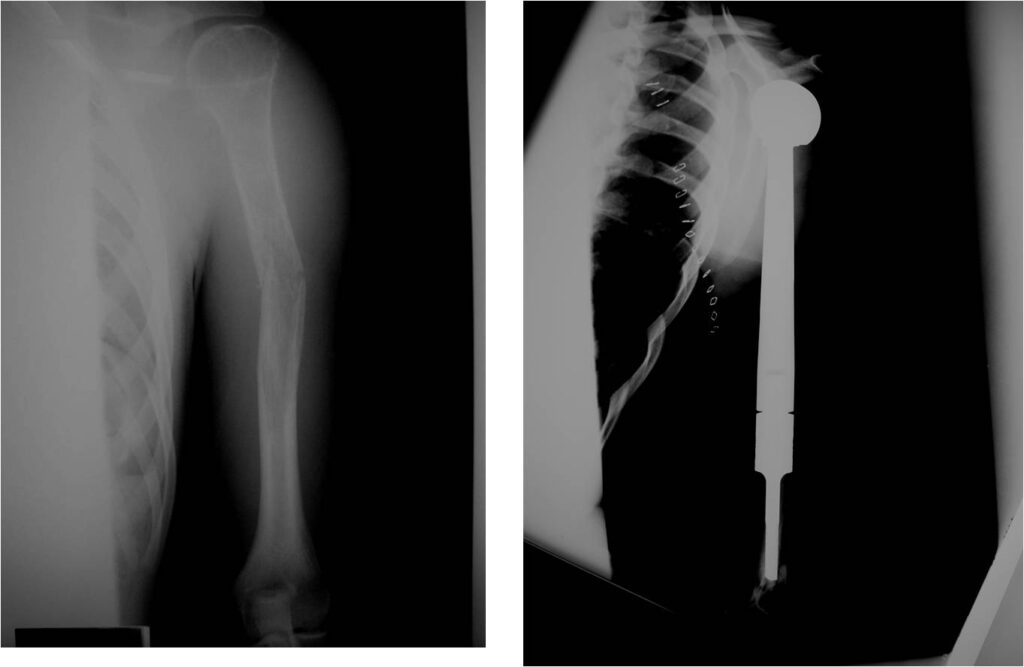

- Permeative or moth eaten bone destruction

- Ill defined and malignant appearing

- Bony changes are often subtle

- Soft Tissue Mass in 90% of of cases

- Periosteal Reaction in 50% of cases

- Onion Skin (colic pattern of irritation)

- Hair on End (rapid continuous lifting of periosteum)

- No cartilage or bone production by tumor

- Pathologic fracture in 10-15%

- Most protocols administer preoperative chemotherapy then surgery is performed. Surgery is followed by several courses of postoperative chemotherapy.

- Ewing sarcoma responds well to chemotherapy. Often there is a dramatic reduction in size of the tumor.

- Surgical resection

- Limb sparing surgery whenever feasible unless there will be a large leg length discrepancy that can not be accomodated for with surgery